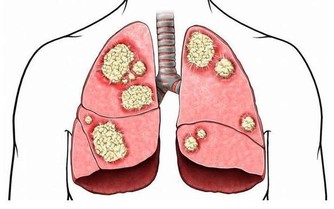

4.防癌抗癌。大蒜中的鍺、硒等,對腫瘤細胞和癌細胞有抑製作用。大蒜中還含有蒜臭素,能夠提高身體免疫力。